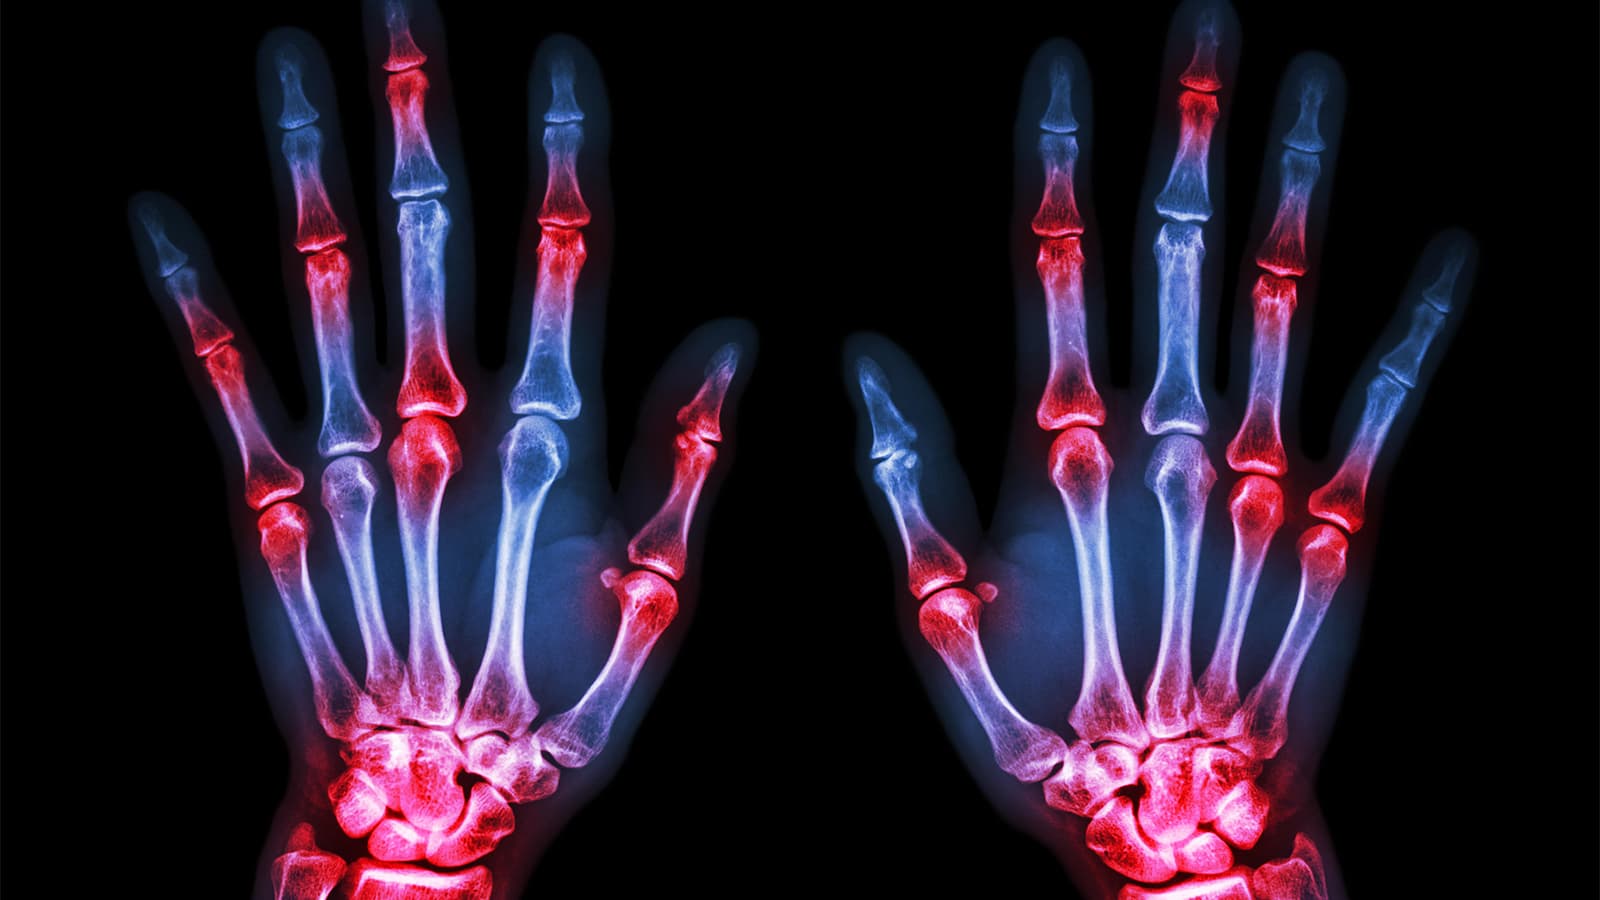

Machine Analyzes Joint X-Rays About as Well as Humans

(MedPage Today) -- A machine-learning system for analyzing rheumatoid arthritis (RA) patients' X-rays was able to produce Sharp/van der Heijde (SvdH) scores, the standard way to quantify joint space narrowing and bone erosions, with good accuracy...